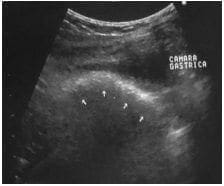

Todos los exámenes de laboratorio fueron normales y en la ecografía abdominal en encontró: dilatación gástrica con engrosamiento de sus paredes (8 mm) y, dentro del estómago, una imagen hiperecoica que se extendía por toda su cara posterior y proyectaba una gran sombra acústica (figura 1).

Estómago con engrosamiento parietalFigura 1. Imagen ultrasonográfica donde se observa dilatación del estómago con engrosamiento parietal e imagen hiperecoica en su interior, que se extiende por toda la cara posterior y proyecta una gran sombra acústica